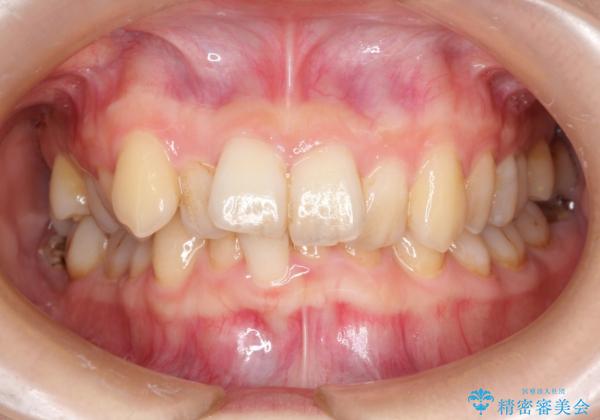

- 前歯の見た目の改善を希望され来院された患者様です。

初診時の歯並びの状態としては、上下ともに前歯部の中等度のがたつきがあり、下の前歯は本来生えるはずの歯が2本生まれつき欠損している状態でした。

また、上顎の歯は虫歯で歯冠が崩壊してしまって保存不可能な歯がありました。

噛み合わせが深い過蓋咬合という状態でもあったため、下の歯の装置をつけたり、嚙み合わせを上げる(下の歯が見える状態にする)ことにたいへんに苦労した症例でした。